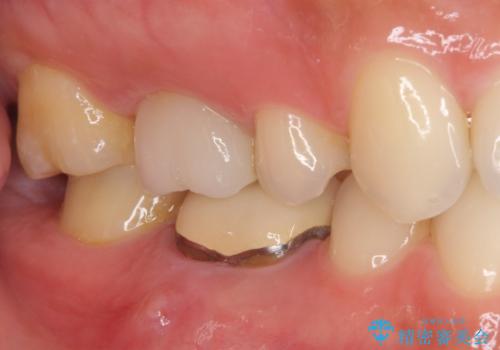

- 奥歯の歯肉から膿が出てくるとのことで来院された患者様です。

膿が出るようになるまでは、咬合時に鈍痛を感じていたとのことで、歯内の感染が原因と考えられました。

レントゲン写真より、根尖部に病変があったことから、根管治療を行い、症状消失後に補綴治療を行うこととしました。